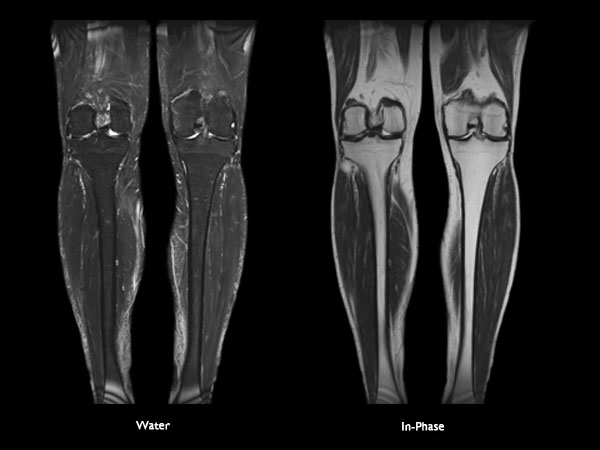

Orthopedic imaging with mDIXON XD TSE